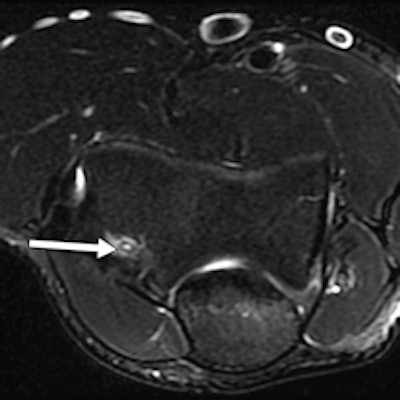

A 20-year-old male weightlifter with flare-up of chronic elbow pain. Coronal proton density-weighted fat-saturated MRI (left) and coronal proton density-weighted nonfat-saturated MRI (right) show anterior bundle UCL midsubstance tear (arrows). Absence of significant edema within disrupted fibers and adjacent soft tissue suggests that tear is chronic.

A 20-year-old male weightlifter with flare-up of chronic elbow pain. Coronal proton density-weighted fat-saturated MRI (left) and coronal proton density-weighted nonfat-saturated MRI (right) show anterior bundle UCL midsubstance tear (arrows). Absence of significant edema within disrupted fibers and adjacent soft tissue suggests that tear is chronic.Of the 28 athletes, 15 were male and 13 female, and the mean age was 25 years (standard deviation 5.2 years), according to Bethapudi, whose co-authors came from the International Olympic Committee in Lausanne, Switzerland, and the department of orthopedic surgery at Oslo University.